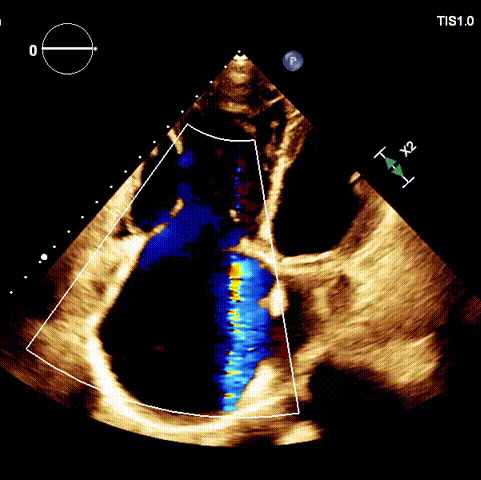

手術在全麻狀態(tài)下開展,海軍軍醫(yī)大學附屬長海醫(yī)院陸方林教授與廈門心血管病醫(yī)院王焱院長共同上臺,為患者進行手術。此次手術采用經右側頸靜脈入路的方式將輸送器送入患者心臟內,在TEE及DSA引導下調整輸送器頭端角度,使得輸送器與三尖瓣瓣環(huán)平面垂直。在輸送器進入右心室后釋放室間隔錨定裝置,而后釋放瓣葉夾持件(2個耳片結構)成垂直狀態(tài)。在TEE及DSA確定夾持件固定至三尖瓣葉根部且位于右室側后釋放人工瓣心房側盤片。隨后調整瓣膜同軸性以及室間隔錨定件位置(貼合室間隔),前推藏針管并固定,進而釋放室間隔錨定裝置,并再次確認瓣膜位置、穩(wěn)定性及同軸性,合攏輸送鞘后撤出輸送器,完成LuX-Valve Plus人工三尖瓣瓣膜的植入。

術后DSA

術后超聲